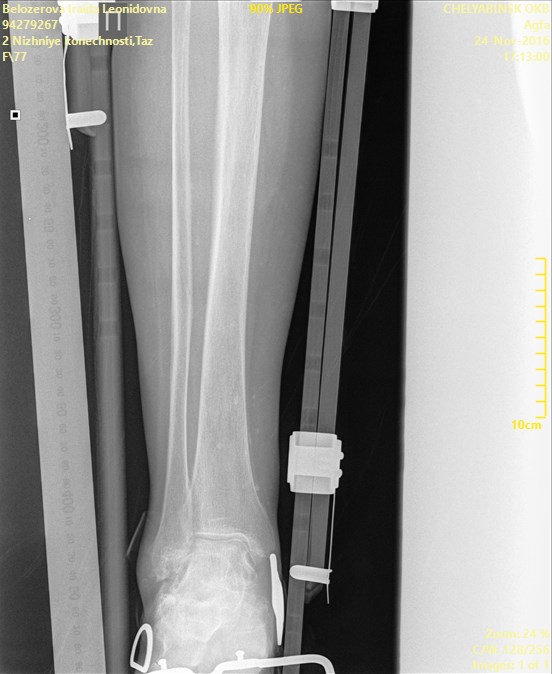

ÎÏÖËÁ   ó÷î   10(ã×ÁÊÍÀÌÌÅÒ)íÁÔÉÓ.   ðÏ   ÎÁÛÉÍ   ÉÚÍÅÒÅÎÉÑÍ  ÏÔ

ÍÅÖÍÙÝÅÌËÏ×ÏÊ ×ÙÒÅÚËÉ ÄÏ ËÏÎÃÁ ÎÏÖËÉ 204ÍÍ. îÏÇÁ ÐÒÁ×ÁÑ

Name: Belozerova_Iraida_Leonidovna_BERZOVYE_AP_CR.jpg